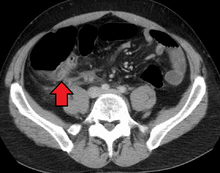

Appendicitis as seen on CT imaging

A CT scan demonstrating acute appendicitis (note the appendix has a diameter of 17.1 mm and there is surrounding fat stranding)

A fecalith marked by the arrow that has resulted in acute appendicitis.

The accurate diagnosis of appendicitis is multi-tiered, with the size of the appendix having the strongest positive predictive value, while indirect features can either increase or decrease sensitivity and specificity. A size of over 6 mm is both 95% sensitive and specific for appendicitis.[49]

However, because the appendix can be filled with fecal material, causing intraluminal distention, this criterion has shown limited utility in more recent meta analyses.[50] This is as opposed to ultrasound, in which the wall of the appendix can be more easily distinguished from intraluminal feces. In such scenarios, ancillary features such as increased wall enhancement as compared to adjacent bowel and inflammation of the surrounding fat, or fat stranding, can be supportive of the diagnosis, although their absence does not preclude it. In severe cases with perforation, an adjacent phlegmon or abscess can be seen. Dense fluid layering in the pelvis can also result, related to either pus or enteric spillage. When patients are thin or younger, the relative absence of fat can make the appendix and surrounding fat stranding difficult to see.[50]